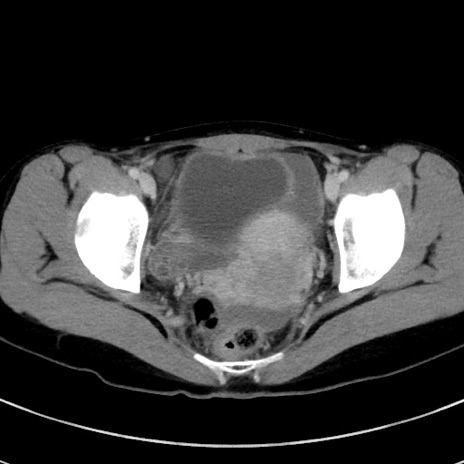

症例17(横断像)

【症例】20歳代女性

【主訴】嘔吐、下腹部痛

【現病歴】昨日夕食後に嘔吐し下腹部痛が出現。本日になっても嘔吐持続し改善しないため来院。

【身体所見】意識清明、BT 37.2℃、BP 108/67mmHg、腹部:平坦、やや硬、下腹部正中から右にかけて圧痛あり、反跳痛軽度あり、tapping pain(+)。

【データ】WBC 13600、CRP 14.94